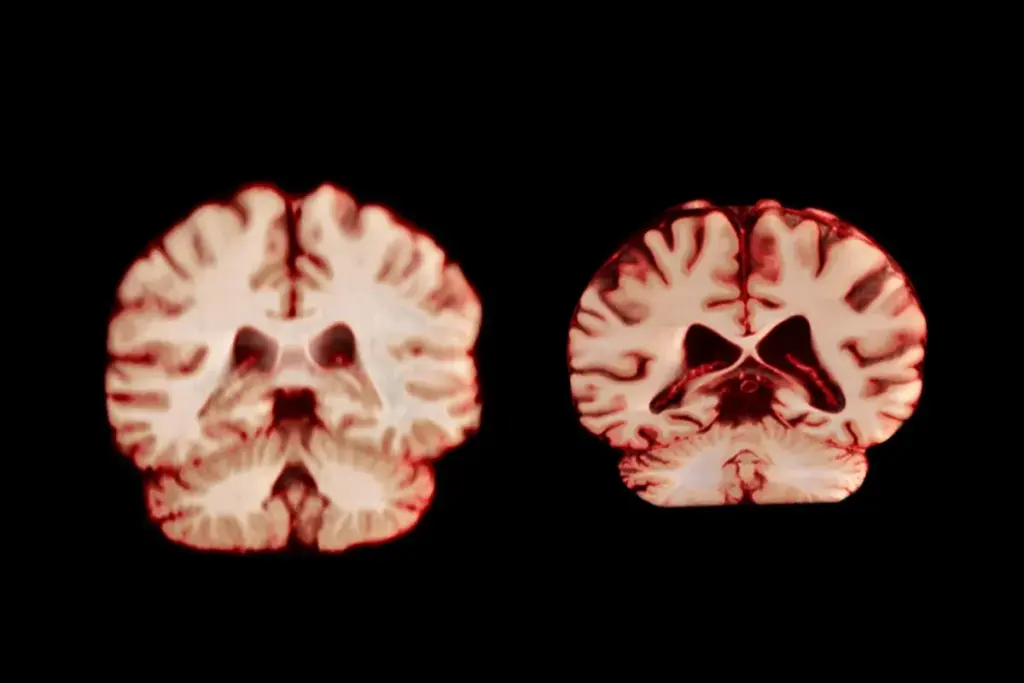

Senile degeneration of the brain is complex, involving many changes. As we get older, our brains naturally change, affecting how we think. But, senile degeneration is a deeper decline in thinking skills, greatly impacting our life quality.

Senile brain degeneration means a drop in thinking skills, like memory loss and problem-solving issues. It’s linked to aging but isn’t just a normal part of growing older. In medical terms, it’s often confused with dementia, but it’s more about brain changes.

It’s important to know the difference between senile degeneration of the brain and dementia. This knowledge helps us give the right care and support to those affected. We’ve talked about what makes senile degeneration unique, like its causes, symptoms, and how it affects people.

Senile debility, linked to aging, can lead to worse cognitive problems. Spotting the signs early and knowing what causes senile degeneration can help doctors and caregivers. They can then offer better support and care.